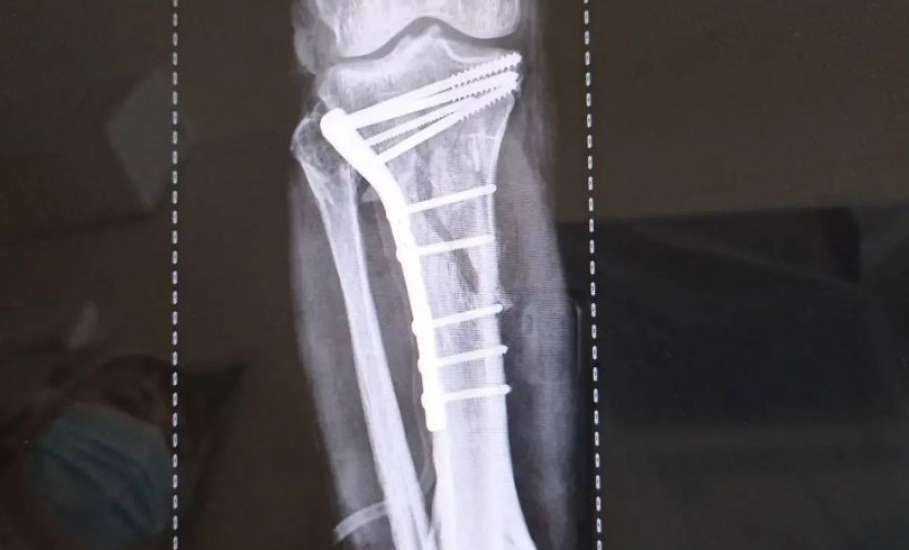

Травматологи горбольницы «Липецк - Мед» почти три часа буквально по кусочкам собирали голени пациента после аварии!

Пациент поступил после тяжелого ДТП 25 февраля с внутрисуставными переломами верхних зон обеих голеней.

Ситуация осложнялась хронической анемией на фоне кровопотери, что требовало особого подхода и скорости.

Заведующий отделением травматологии Дмитрий Соколов с ассистентом, врачом - травматологом Евгением Крюченковым провели одномоментное оперативное  вмешательство на двух конечностях с интраоперационной гемотрансфузией. То есть, оперировали одновременно обе ноги с минимальной кровопотерей.